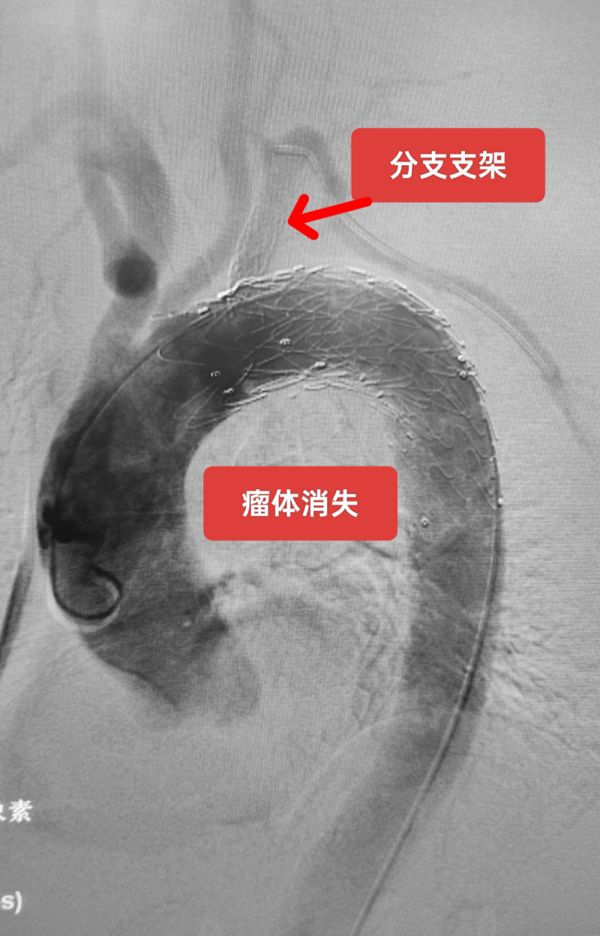

最终的手术达到了预期效果,患者康复出院。这也是我院首次开展此类手术,该手术成功进行提升了血管介入科治疗血管疾病服务广大患者的能力水平,也为我院介入医学进一步发展奠定了扎实基础。